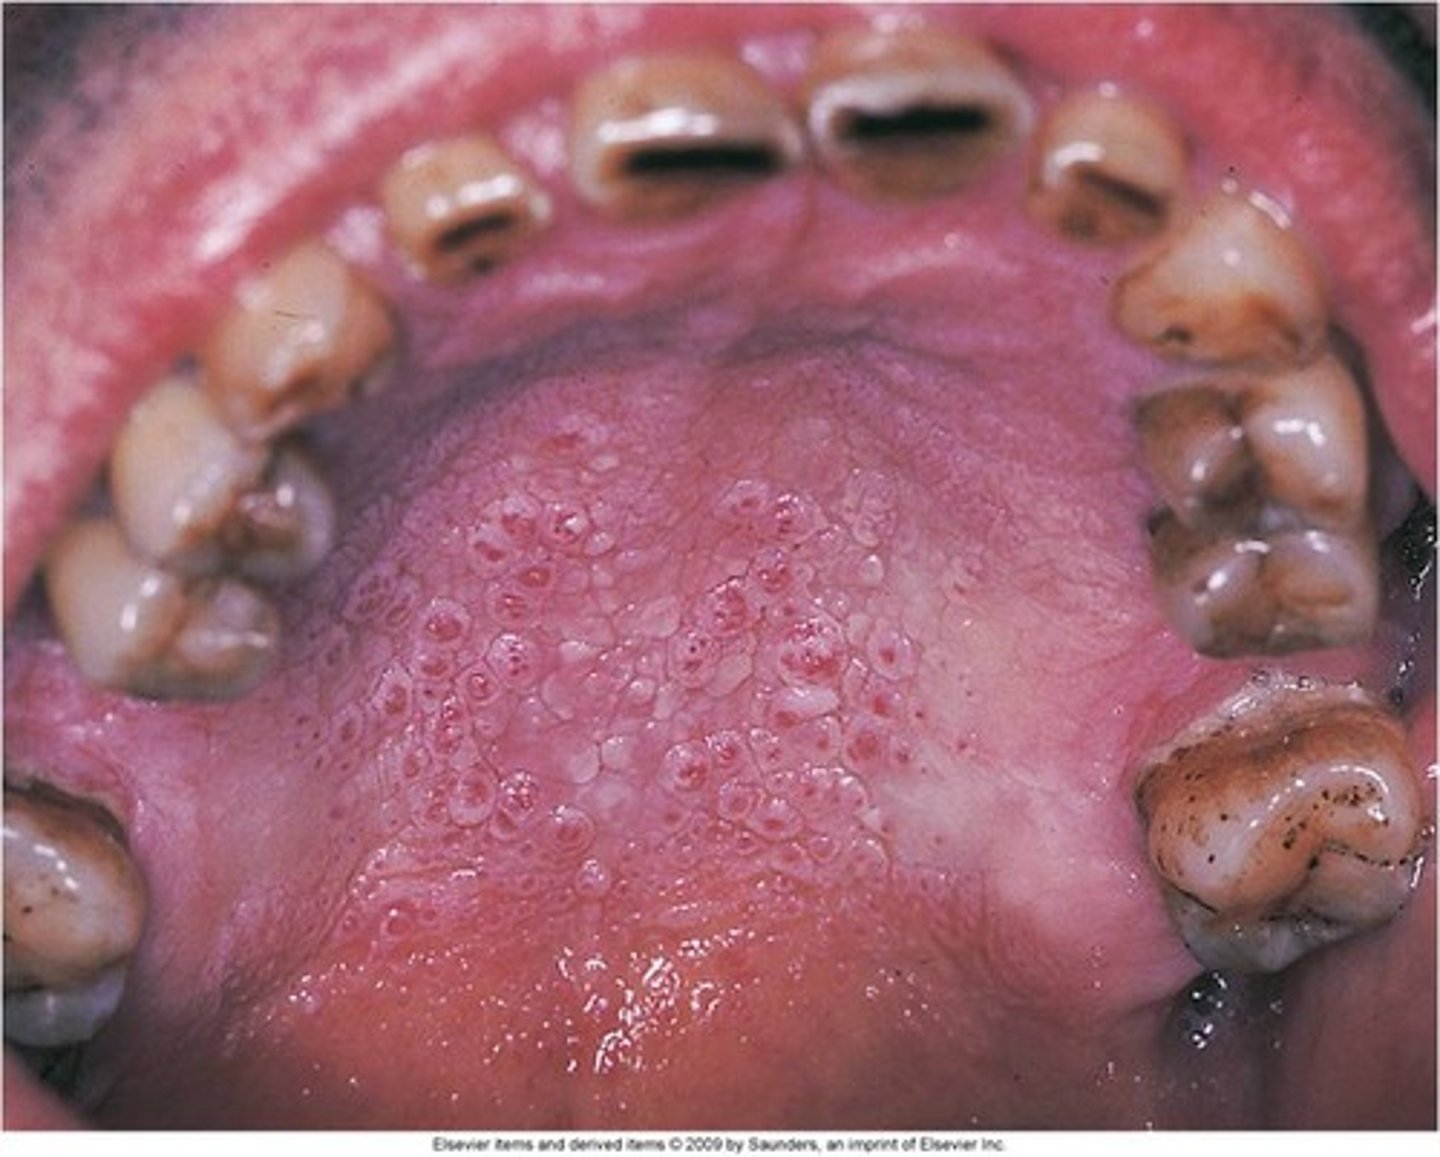

Name the pathology: picture of palate with numerous small raised areas with central red dots caused by pipe smoking

This is not premalignant and is caused by the ____ form the smoke. Not the chemicals

tx?

nicotonic stomatitis

heat from the smoke, not the chemicals

is reversible, need to stop smoking

Name the pathology: can be seen on the palate in a pipe smoker

nicotonic stomatitis